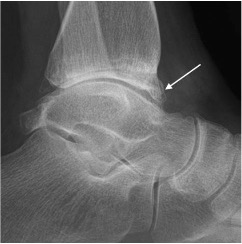

Anterior impingement with anterior distal tibial osseous spur (arrow)

Posterior impingement

Can be caused by:

- prominent os trigonum

- Stieda process (elongation of the lateral tubercle of the posterior talar process)

- posterior talar fracture

- ossification

- soft tissue impingement between the posterior tibia and talus on plantar flexion

Posterior impingement with prominent os trigonum (arrow)